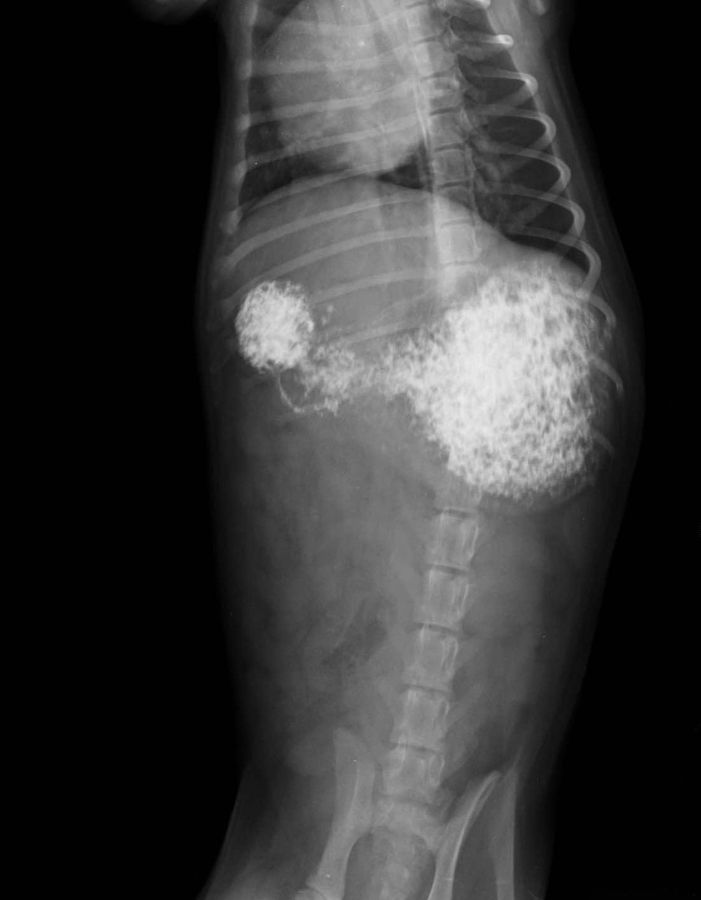

Die kleine SHANIA hat ein paar wirklich schwere Tage hinter sich. Ihr Magen war stark verstopft und bereits deutlich geweitet, eine Operation stand im Raum. Sie wurde geröntgt, in die Klinik gebracht und intensiv medizinisch betreut. Zum Glück konnte ein chirurgischer Eingriff vermieden werden.